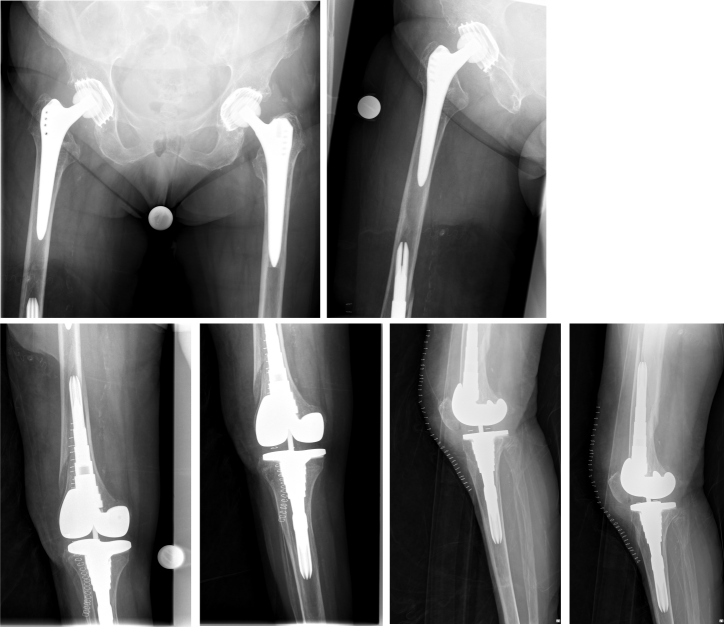

The surgical procedure for subtotal replacement of the femoral diaphysis was performed without any intra- or postoperative complication. The duration for the surgical intervention was one hour and 40 minutes. The patient was then mobilized with full weight bearing supervised by physiotherapists at ward level, which she tolerated well. The pain was significantly relieved during hospital stay. The postoperative radiographs showed correct implant position and a satisfactory surgical result (Figure 6 [Fig. 6]).

Figure 6: The postoperative radiographs showed correct implant.

At one-year follow-up, the patient did not complain of any pain. The Harris Hip Score HHS improved from 26 (prior to partial diaphyseal replacement) to 83 at one-year follow-up (Figure 7 [Fig. 7]), the Western Ontario and McMaster Universities Osteoarthritis Index WOMAC improved from 88 to 16. The range of motion of the right hip joint one year after surgery was: extension/flexion 0/0/90°, abduction/adduction 30/0/20°, external rotation/internal rotation 30/0/20°. The range of motion of the right knee joint one year after surgery was: extension/flexion: 0/0/120°. There were no symptoms or signs of infection or any other complications.

Figure 7: Postoperative radiographs one year after surgery without any morphological changes compared to postoperative radiographs